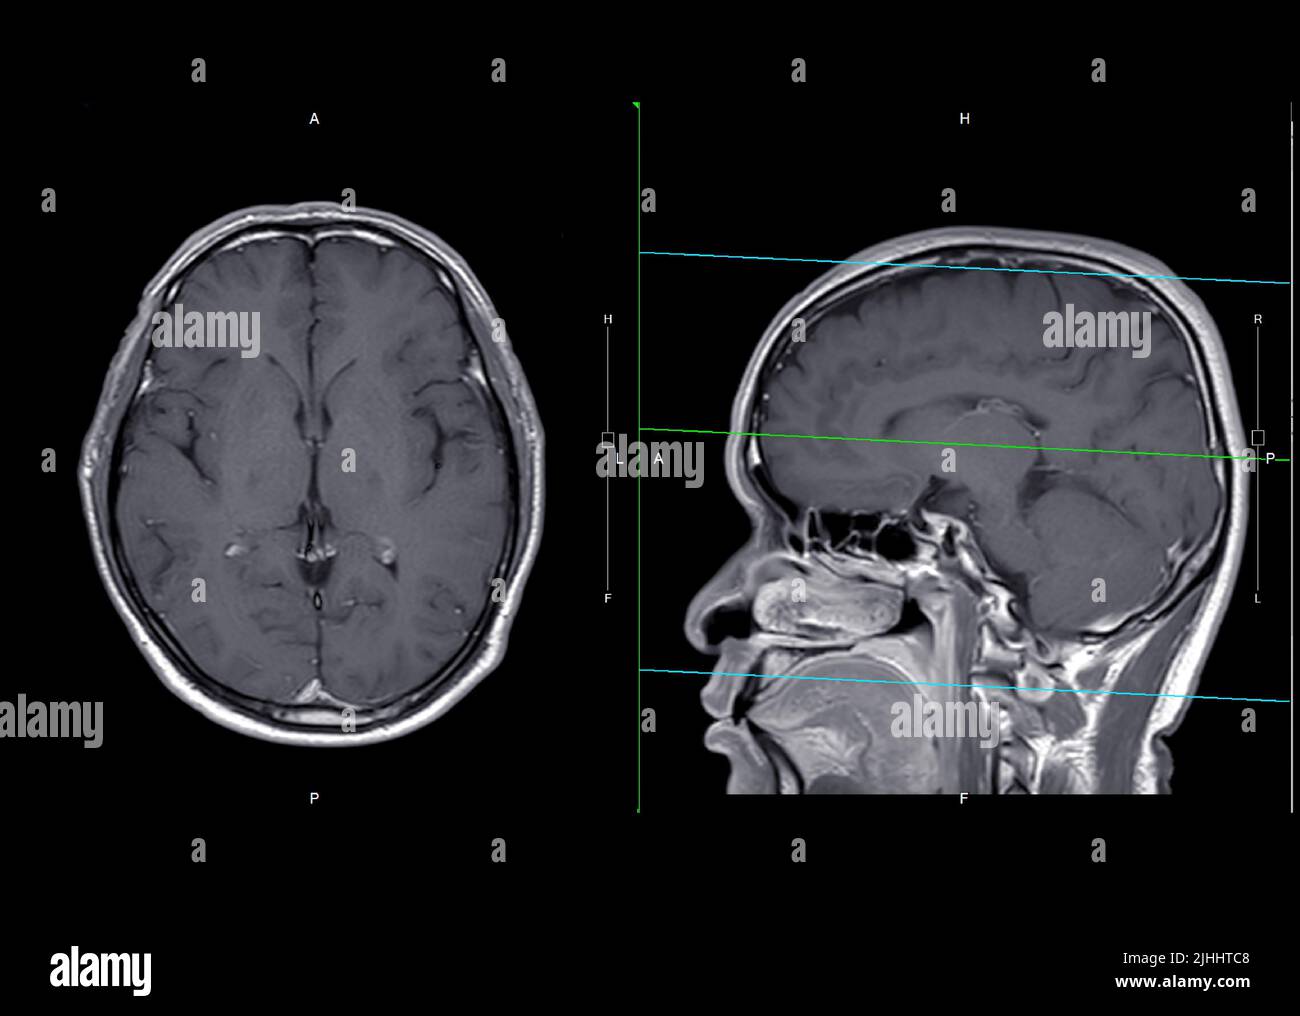

MRI brain axial and sagittal plane with gadolinium contrast for detect

MRI brain axial and sagittal plane with gadolinium contrast for detect What Can Mri Brain Detect Mri is often used to detect brain tumors because it shows the brain more clearly than do other imaging tests. Mra can also be used to detect intracranial (within the brain) aneurysms and vascular malformations (abnormalities of blood vessels within the brain, spinal cord, or other parts of. This information can help guide. A variant called mr angiography (mra) provides.. What Can Mri Brain Detect.